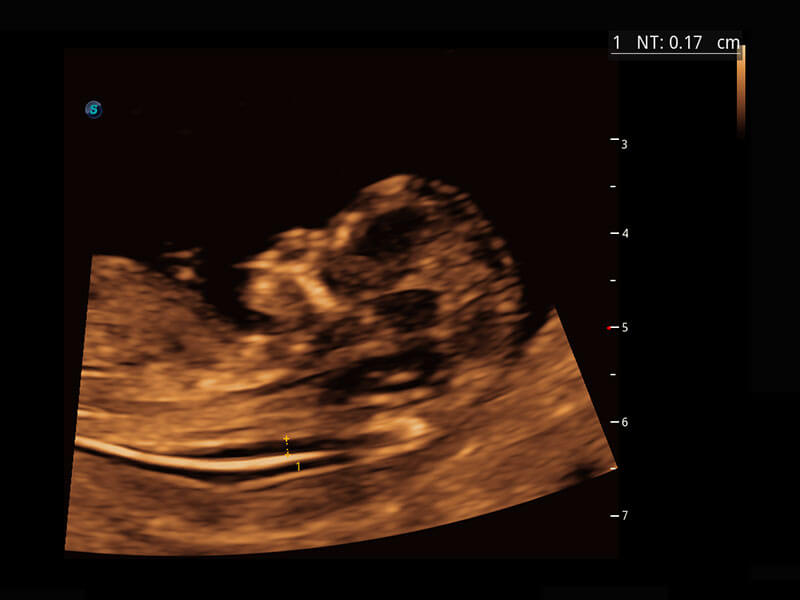

P60在胎兒早孕期超聲篩查中為您帶來優(yōu)異的圖像質(zhì)量。

早孕-胎心